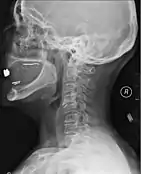

A radiographic evaluation using an X-ray, CT scan, or MRI can determine if there is damage to the spinal column and where it is located.[9] X-rays are commonly available[85] and can detect instability or misalignment of the spinal column, but do not give very detailed images and can miss injuries to the spinal cord or displacement of ligaments or disks that do not have accompanying spinal column damage.[9] Thus when X-ray findings are normal but SCI is still suspected due to pain or SCI symptoms, CT or MRI scans are used.[85] CT gives greater detail than X-rays, but exposes the patient to more radiation,[87] and it still does not give images of the spinal cord or ligaments; MRI shows body structures in the greatest detail.[9] Thus it is the standard for anyone who has neurological deficits found in SCI or is thought to have an unstable spinal column injury.[88]